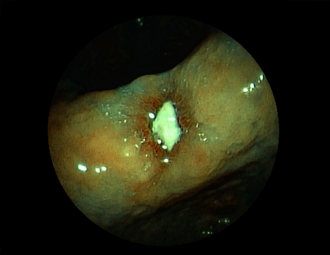

症例1:胃潰瘍(37才、男性)

①胃潰瘍(Stage A1)

健診:胃レントゲン検査で、胃角部ニッシェを指摘され当院受診。

胃角部小弯に、深くて大きな、大きさ約10mmの胃潰瘍(stage 1)

があり、潰瘍底は一部白苔はみ出しを認める。エソメプラゾールマグネシウム水和物投薬で治療開始しました。

(FICE+インジゴカルミン散布画像)